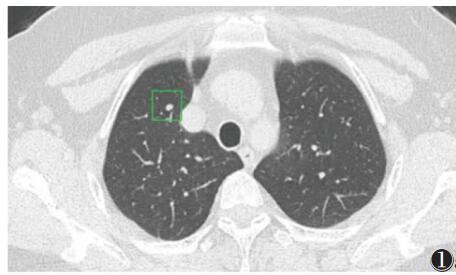

人工智能辅助低、高年资规培医师对CT肺结节检测效能的对比研究

目的:探讨不同年资规培医师在 CT 独立阅片及应用人工智能辅助阅片模式下对肺内结节的检测效能是否有差异,并分析低年资规培医师在应用人工智能辅助阅片后,能否达到高年资规培医师对肺结节的检测水平。 方法:收集 180 例患者的胸部 CT 图像,分别由 2 名低年资、2 名高年资规培医师进行独立阅片并标注肺结节,经过 2 周洗脱期后,再次对相同病例借助人工智能软件进行阅片并标注结节,记录结节的位置、大小、密度及标注时间。 将各组标记结果与金标准进行比较,记录真阳性、假阳性及假阴性结节数,计算结节检测敏感度及人均假阳性结节数。 采用 Kappa 检验分析低、高年资规培医师对肺结节检测的一致性,采用 Wilcoxon 秩检验(配对样本)比较低、高年资规培医师独立阅片及借助人工智能辅助阅片的诊断敏感度、人均假阳性结节数和阅片时间。